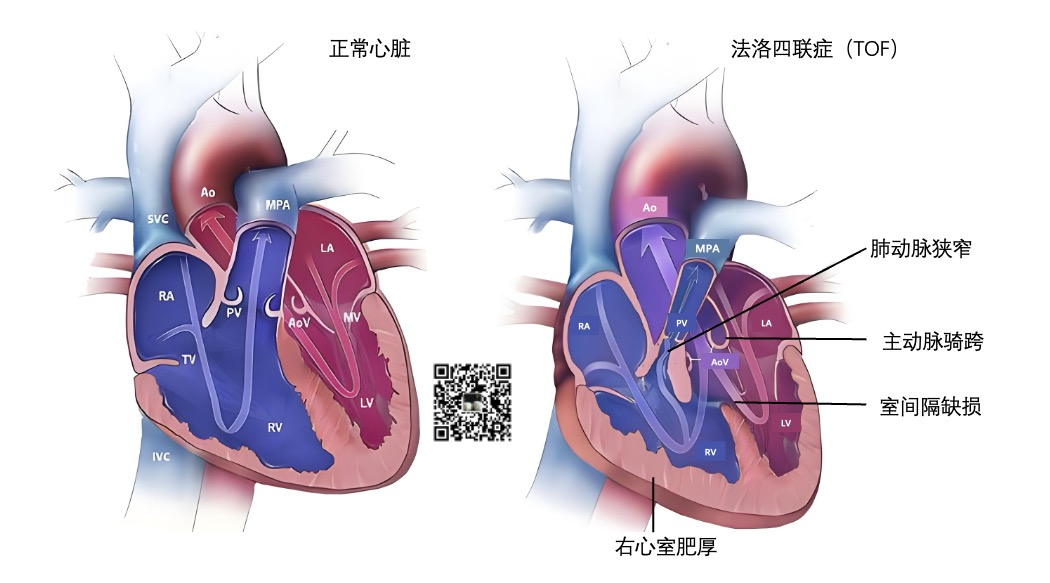

结构性心脏病是指解剖异常引起心脏内部组织及其发出血管的改变而造成心血管解剖、病理生理的变化。

正常的心脏的解剖结构如下图:

可以看到心脏有以下4个心腔(chamber),位于心脏上方的心房(ateria)较小,位于心脏下方的心室(ventricle)较大。

先天性心脏病主要包括室间隔缺损、房间隔缺损、动脉导管未闭,法洛氏四联症等。

法洛四联症(Tetralogy of Fallot,TOF)是一种常见的先天性心脏畸形。其基本病理为室间隔缺损、肺动脉狭窄、主动脉骑跨和右心室肥厚。